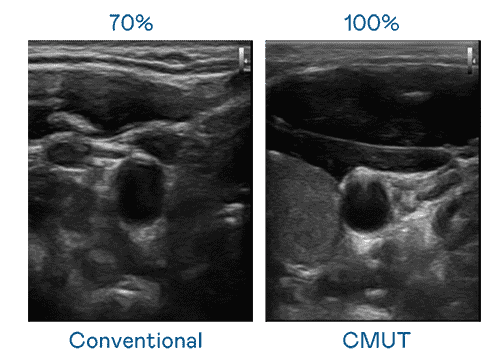

CMUT 技术是一种用电容式微机电元件来产生超音波讯号的技术。。。。与传统 PZT 压电式技术相比,,,CMUT 频宽增加 30%,,更宽频的超音波讯号让影像解析度大幅提升,,,,是实现高影像品质医疗超音波扫描、、、、促进精准医疗发展的关键技术。。。

大频宽带来超清晰影像

超音波影像的解析度高低,,,,首先取决于探头能发出的讯号频宽。。。。优游UB8 CMUT 可提供高清晰的超音波讯号,,,提供高频宽、、高灵敏度、、、、影像纹理细节更高的超音波影像,,,,协助医护人员缩短影像判读时间及利用精准的医疗影像进行诊断。。。。